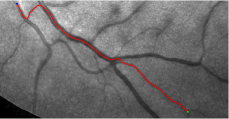

Validation. We validate our minimal path model on respective 54 and 30 patches obtained from the DRIVE [14, 15] and the IOSTAR [16] datasets with AV groundtruth. Each artery involved in these parches locates near a vein or crossing it at least once. Our goal is to extract the artery between two given points. In order to get the quantitative evaluation, we first convert each continuous spatial path to an 4-connected digital path which is considered as a pixel collection. We denote by the collection of digital path pixels inside the artery groundtruth map . Thus, a measure can be simply defined as , where and mean the respective number of elements involved in and . We compare our model to four existing minimal path models: the isotropic Riemannian (IR) model [1], the anisotropic radius-lifted Riemannian (ArR) model [4], the isotropic orientation-lifted Riemannian (IoR) model [5] and the curvature-penalized (CuP) model [7]. The construction of these metrics are based on the OOF outputs [12]. Note that a centerline-based potential is chosen so that we remove the radius dimension of [5] to reduce computation complexity. The results in terms of the score are presented in Table 1, including the average (Avg.), maximum (Max.), minimum (Min.) and standard deviation (Std.) values. In both DRIVE and IOSTAR datasets, our method can achieve the best performances thanks to the coherence penalization. Note that in Table 1, we evaluate our method by using the refined paths instead of using the original coherence-penalized minimal paths. For comparisons in visualization, we show the minimal paths from the ArR metric , the CuP metric and the proposed coherence-penalized metric on three retinal patches as shown in Fig. 3. The targeted artery vessels which cross veins at least once are labeled by red color in column 1. The paths shown in column 4 from the proposed metric are results after refinement. One can claim that our method indeed can catch expected arteries while other metrics fall into the traps of short branches combination.